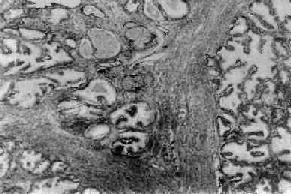

图14-3 前列腺增生 腺体平滑肌和纤维组织均呈明显增生,有些形成乳头状突入腺泡腔内,有些腔内含有分泌物

图14-2 前列腺增生症 前列腺明显肿大,压迫膀胱颈部,且部分突入膀胱三角区;膀胱扩张肥厚,粘膜面可见代偿肥大的平滑肌条索呈梁状 镜下,可见前列腺的腺体、平滑肌和纤维结缔组织呈不同程度增生(图14-3)。一般认为前列腺增生是先在尿道两侧的粘膜下,纤维及平滑肌增生,形成多数的小结节状,以后腺体也相继增生,夹杂于增生的平滑肌与纤维组织之间而逐渐形成大小不等的、由纤维及肌组织包绕的腺体结节。增生的腺体腺泡数目增多,体积也呈不同程度扩大。上皮细胞呈柱状或立方形,核位于基底部,也可形成乳头状突入腺泡腔内。腺泡腔内有分泌物及脱落的上皮细胞,偶可见淀粉样小体。纤维及平滑肌细胞肥大、增生,包绕或穿插于增生的腺体之间,形成宽窄不一的间隔。间质中可见多少不等的淋巴细胞浸润。 前列腺增生常引起排尿障碍和继发感染,约有半数患者需要进行治疗才能解除痛苦。